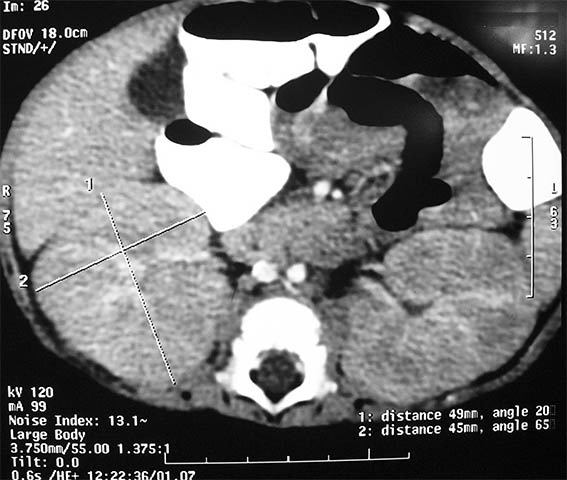

A five month-old girl presented with symptoms of malnutrition and severe urinary tract infection, with signs of sepsis and acute renal failure: serum creatinine 1.4 mg/dL. Both blood and urine cultures were positive for Escherichia coli, and antibiotic therapy was started. Severe, almost symmetrical, bilateral nephromegaly was evident on computed tomography (Figures 1 and 2). Voiding cystourethrography showed no urinary tract abnormalities.

Figure 2.